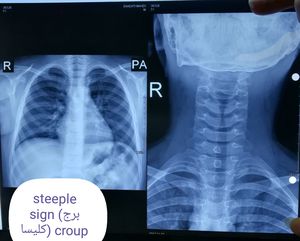

Croup

Steeple

Signe